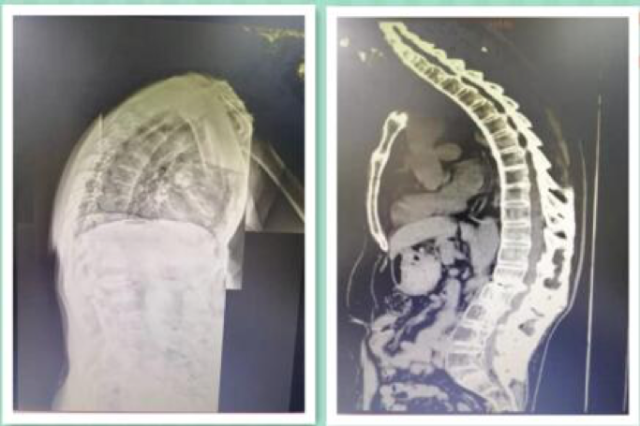

一位 51 岁的男性患者王某,长期受强直性脊柱炎折磨,不仅驼背,整个脊柱像一根竹竿一样硬,后来腰椎又出现了骨折,伴有硬脊膜的骨化,左下肢神经受压,常年靠拐杖行走 2019 年 8 月中旬,当他驼着背来到桂医附院后,一台手术让他挺直腰杆康复出院。

手术前

该手术由北京协和医院赵宇教授主刀,脊柱骨病外科刘瑞端副主任医师等人协助,共同为患者行强直性脊柱炎后路环脊髓 360 度减压、截骨后凸矫形、椎弓钉内固定术。

患者骨质异常坚硬,相关解剖结构不能辨别,置钉异常困难,术中发现硬脊膜骨化,和椎板等骨性结构粘连严重,同时为了达到良好的神经减压效果和避免术后神经并发症,术中将骨化的硬脊膜切除,术中损伤神经的风险巨大,手术时间长达五个小时。

术后患者没有出现严重神经损伤并发症,患者的腰板也挺直了,可自行行走,已经康复出院。患者家属给脊柱骨病外科送来一面锦旗,深表谢意。

手术后